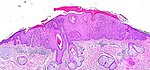

Layers of the skin

- Epidermis - outer most layer, avascular, separated from dermis by a basement membrane, epithelial tissue.

- Dermis - below the epidermis, vascular, separated from the epidermis by a basement membrane, connective tissue.

Epidermis

Layers of the epidermis

Epidermis layers - from the surface to epidermal-dermal junction:

- Stratum corneum.

- Stratum lucidum.

- Present only in "thick" skin.[4]

- Stratum granulosum.

- Stratum spinosum (aka prickle layer).

- Stratum basale (germinativum).